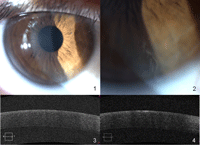

Dos meses más tarde, el día de la operación, la opacidad central había desaparecido por completo. Quedaba una lesión mucho menor (Figura 3) con características similares en el cuadrante ínfero-nasal de la córnea y en relación al limbo. Las imágenes de OCT (Figura 3) muestran un aclaramiento completo del epitelio corneal central y un pequeño trozo de epitelio hiperreflectivo con escasos espacios hiporeflectivos. La AV se mantuvo en movimientos de mano OD y 0,5 mejorando a 0,6 con estenopeico en OI, la falta de mejoría en la AV dio lugar a la sospecha de pérdida de visión funcional. La sospecha fue confirmada en una visita a neurooftalmología 2 meses más tarde con el hallazgo de una AV no corregida de 1.0 en cada ojo. El examen ocular permaneció sin cambios.

Figura 3. Aspecto en la visita de seguimiento. 1. Desaparición de opacidad central, pequeña zona de microquistes infero-nasal. 2. Detalle de la zona afectada. 3. OCT normal del epitelio central. 4. OCT de la lesión residual que muestra el patrón descrito con hiperreflectividad y microquistes.